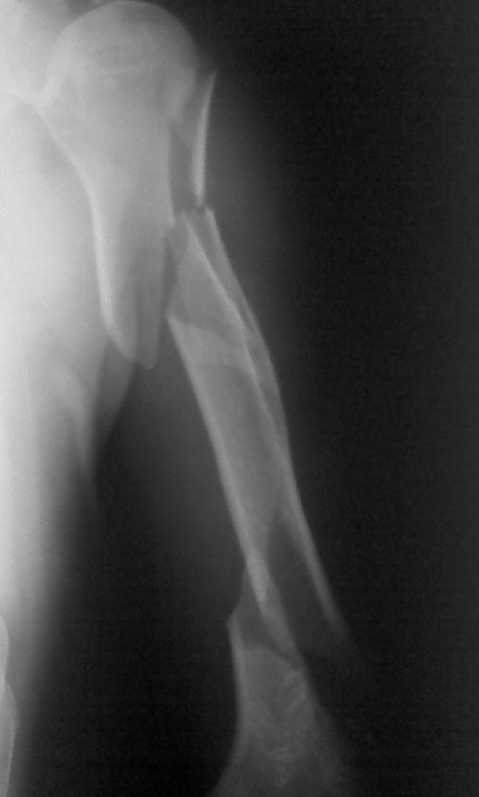

Сложный перелом плечевой кости

Мужчина 54 лет поступил в отделение в послепраздничные дни с вот таким сложным и редким переломом плечевой кости (см. рентгенограммы). Перелом получен во время эпиприпадка. Мы понимаем, что методом выбора в данном случае является БИОС, однако в нашем лечебном учереждении это исключено по разным причинам: во-первых, нет ЭОПА, а во-вторых, администрация категорически против покупки фиксаторов больными (вплоть до увольнения)- в таких условиях приходится "работать". В нашем распоряжении есть обычные пластины, штифты Кюнчера, титановые штифты (заготовки), аппараты Илизарова. Пока больше склоняемся к выполнению остеосинтеза двумя пластинами: первая передне-наружным доступом сверху, а вторая задним доступом снизу... Как вы смотрите на этот вариант остеосинтеза, какие есть альтернативы исходя из наших условий??? Подскажите....!!! Ваши коментарии мы внимательно изучим и на основании их примем окончательное решение! Заранее СПАСИБО!!!